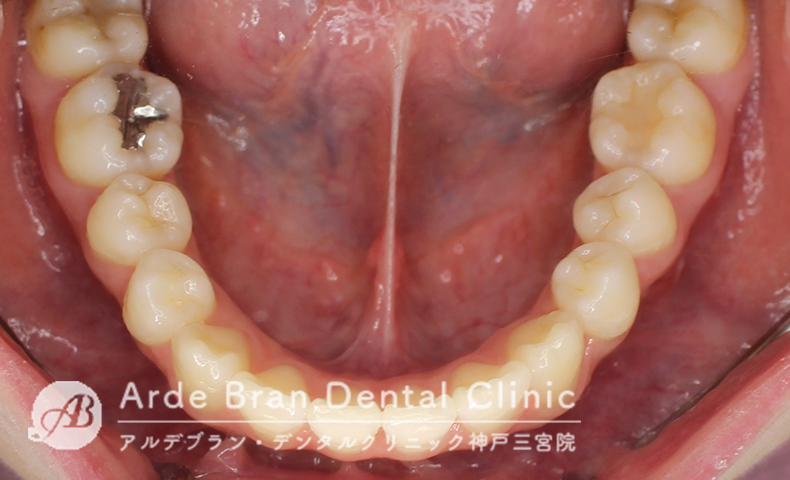

- 叢生(20代女性 治療期間7カ月)

- 下の歯のがたつきを治したいとの事でご来院されました。他院では下の歯はがたつきの量が多いため並べると反対の咬み合わせになるため抜歯矯正が必要で2年かかると言われたそうです。当院で精査した所、側貌も問題なかったため、奥の歯を後ろに動かし、アーチを少し広げ、IPRを入れる(歯と歯の間を少し削る)事によって非抜歯にて治療が可能と診断しました。目立たない装置をご希望のためインビザラインにて治療を行いました。非抜歯にて治療が完了出来て、かつ治療期間も短く終えられました。

- 治療前

- 治療後

| 装置名 | インビザラインフル |

| 抜歯非抜歯 | 非抜歯(下顎の親知らずのみ抜歯) |

| 治療期間 | 7カ月 |

| 費用 | インビザラインフル72万円+TAX |

| リスク副作用 | 装置装着による違和感、歯の移動時の痛み、歯根吸収など。詳しくはこちらをご参照ください。 |